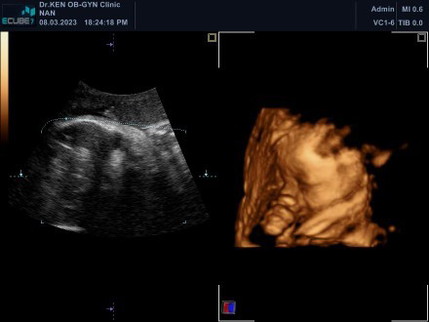

36w2d อัลตราซาวด์4มิติ

ไม่ยอมให้เห็นหน้าเลย แอบหวังจมูกจะโด่งเหมือนในภาพไหมแม่ๆ5555 เอาภาพมาโชว์แลกเปลี่ยนกันจ้า ใครคลอดแล้วภาพตรงปกบ้าง